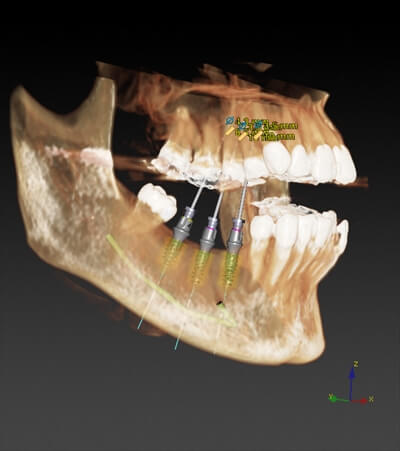

実際の症例1:右下に3本のインプラントを予定

①設計前のCT画像です。

②下顎の神経に当たらないように3本のインプラントの位置を確認します。